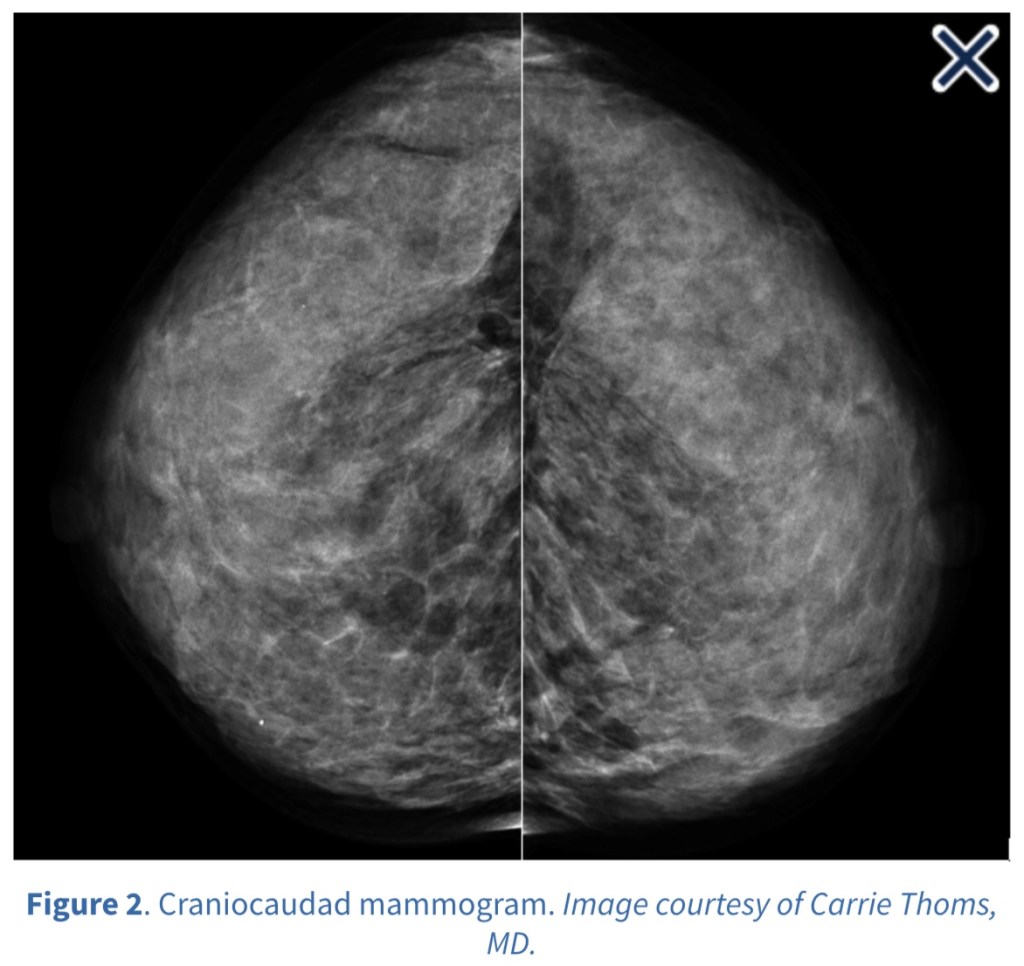

- Both tomosynthesis and breast ultrasound are additional techniques for enhanced screening in patients with dense breasts

- Multiple studies show significant benefits from the addition of tomosynthesis to conventional digital mammography alone in screening programs: